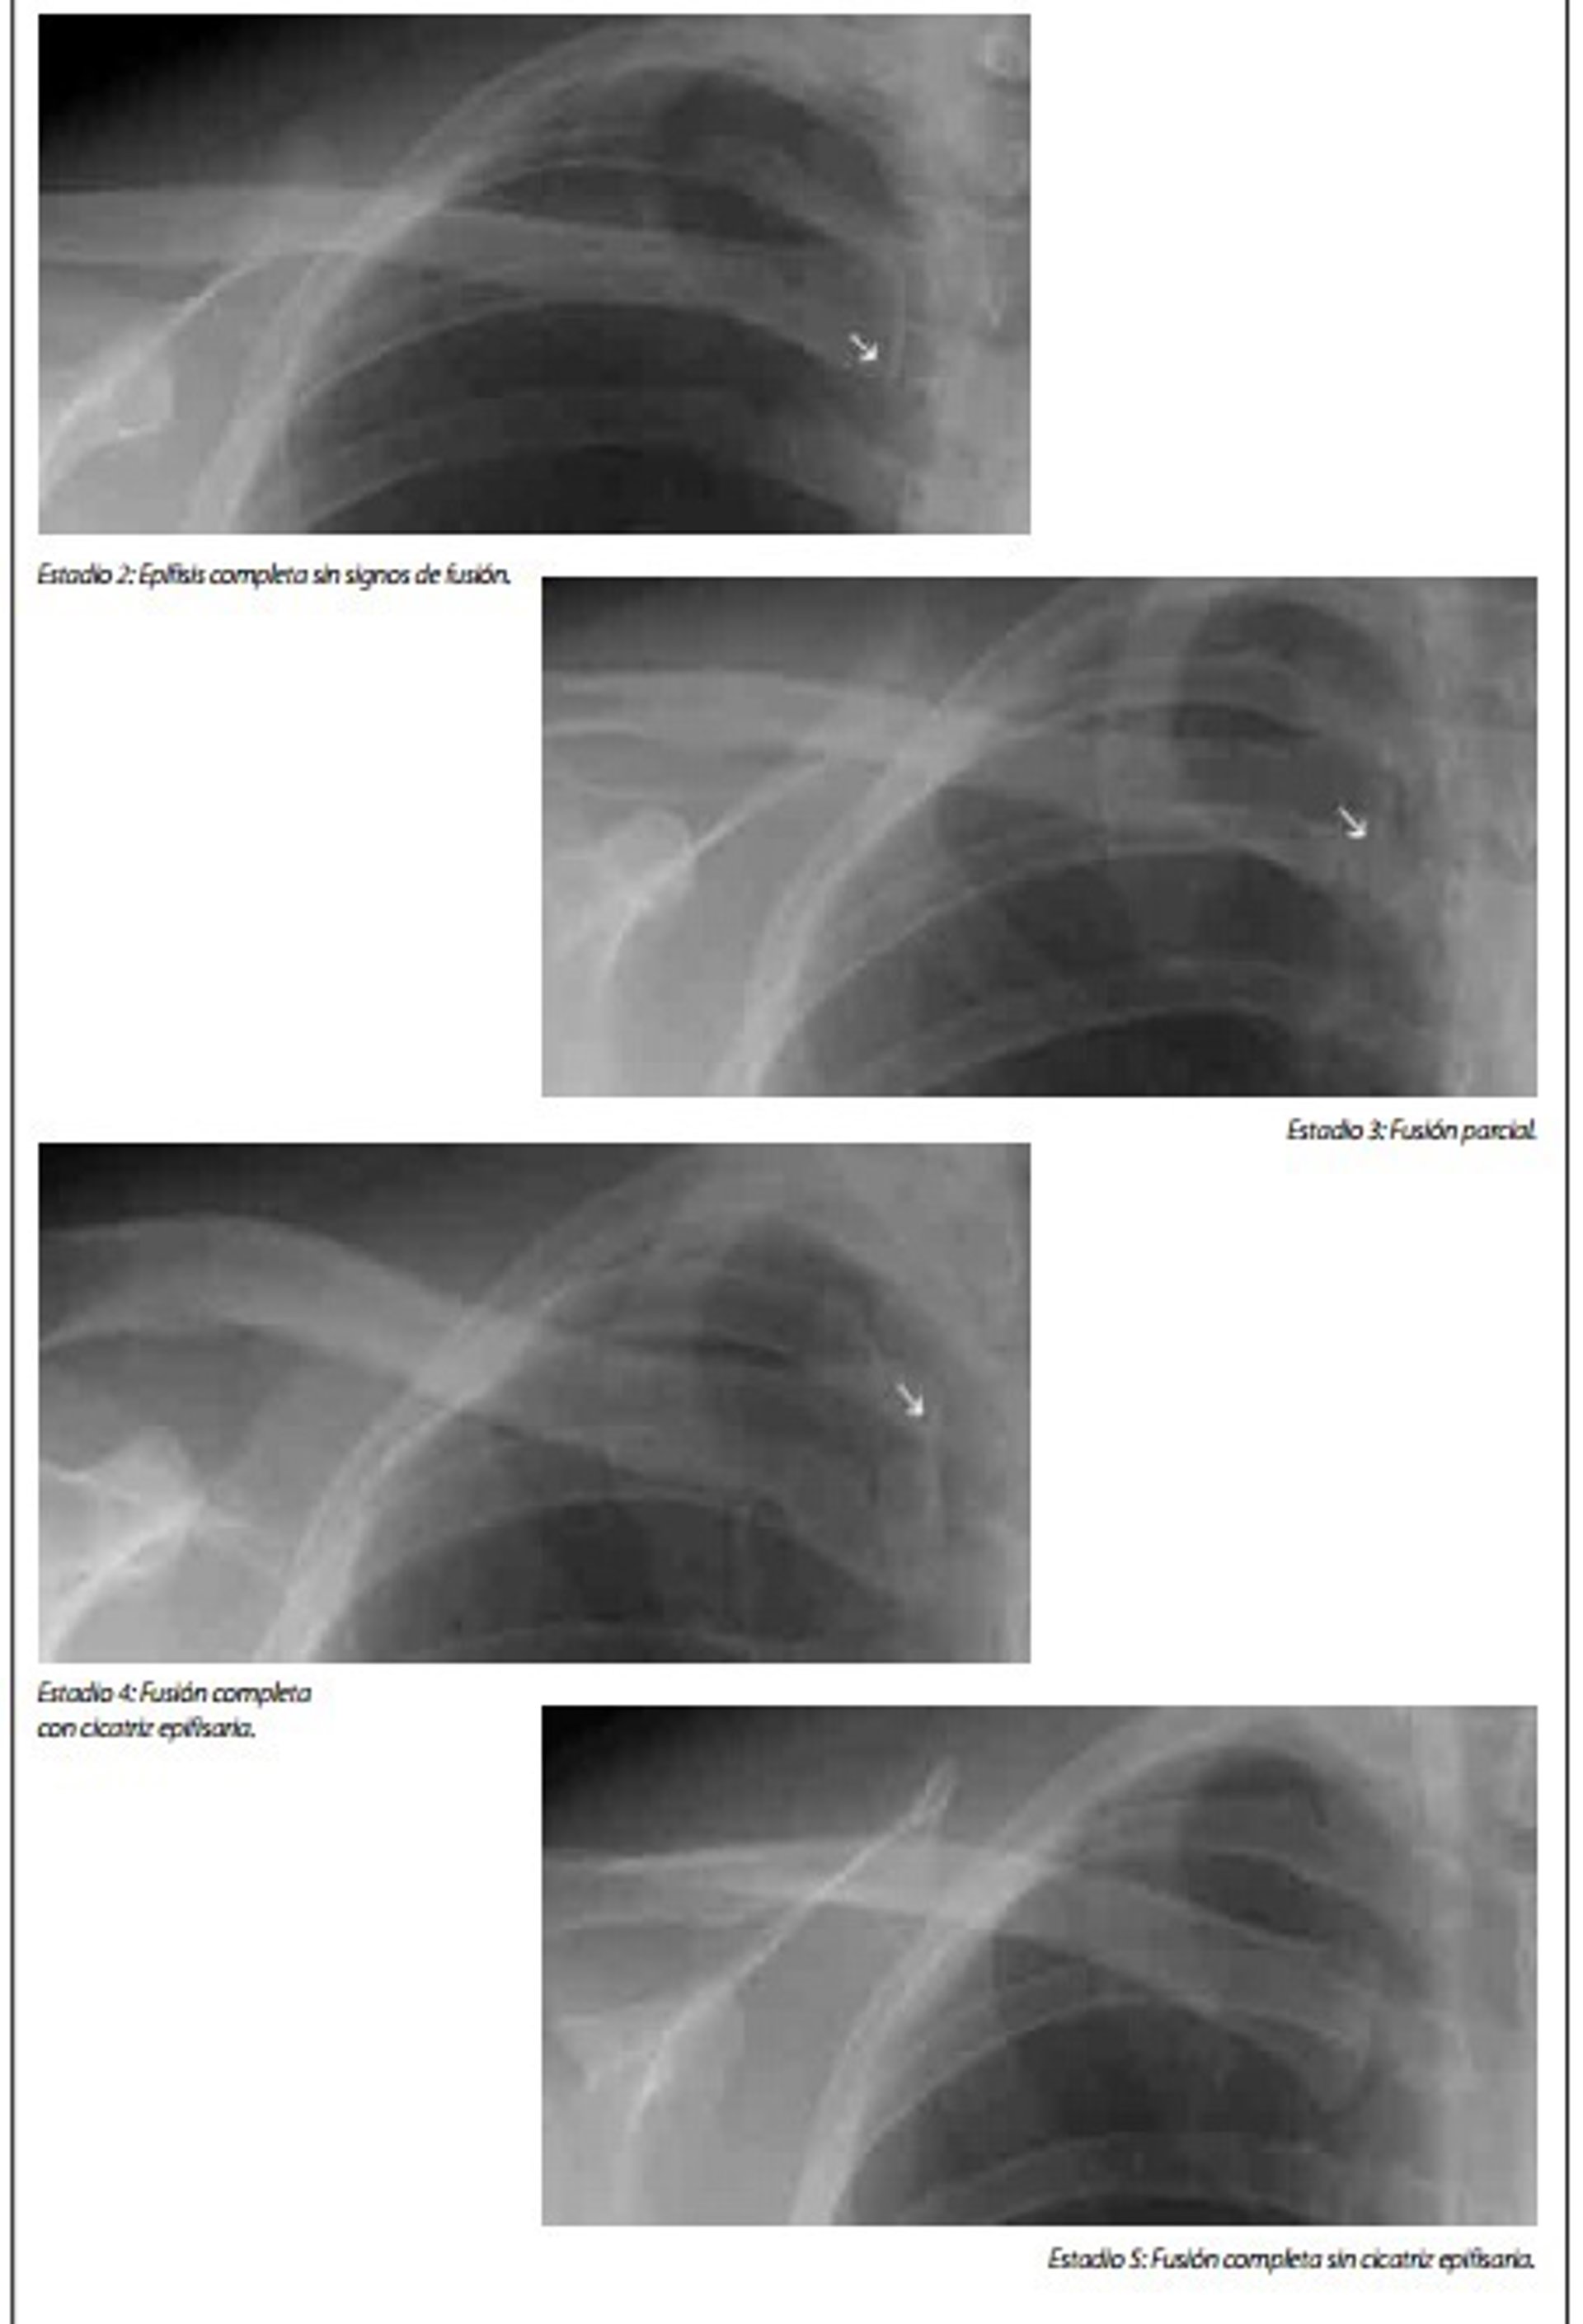

Pruebas oseométricas de determinación de la edad, no acompañados